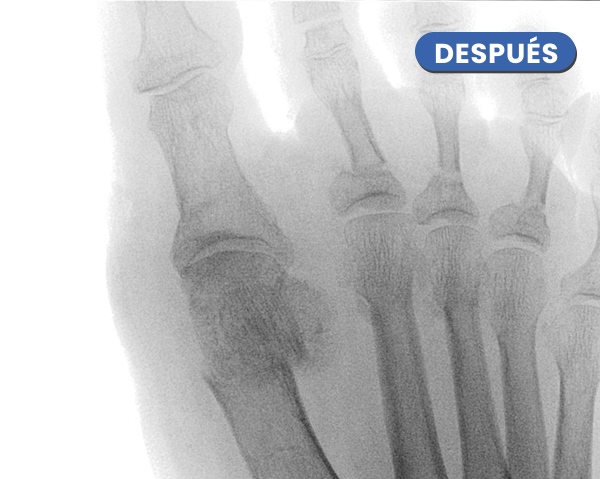

Lo llamativo de la imagen postquirugica inmediata es la corrección biomecanica que se ha ejercido colocando la cabeza del metatarsiano que se encontraba luxada dentro de la zona articular de los sesamoideos.